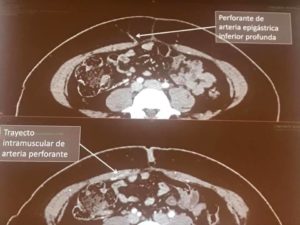

Первый курс ICPF был организован в г. Гент, Бельгия 20 лет назад, на заре применения перфорантных лоскутов в реконструктивной хирургии. Сейчас перфорантрные лоскуты можно назвать наиболее распространенной техников в этой ветви хирургии, а само мероприятие переросло в крупный международный форум.

Уникальная черта этого курса – обмен опытом в хирургии с использованием перфорантных лоскутов – хирургическими приёмами и тонкостями, техниками и т.п. в дружеской атмосфере. Программа курса насыщена лекциями по различным видам перфорантных лоскутов, особенностям планирования операций и подготовки лоскутов, операциями и кадавер-демонстрациями. Среди изюминок курса – выполнение гуру реконструктивной хирургии, профессором Исао Кошима (Isao Koshima), лимфо-венозных анастомозов у пациентки с лимфедемой.